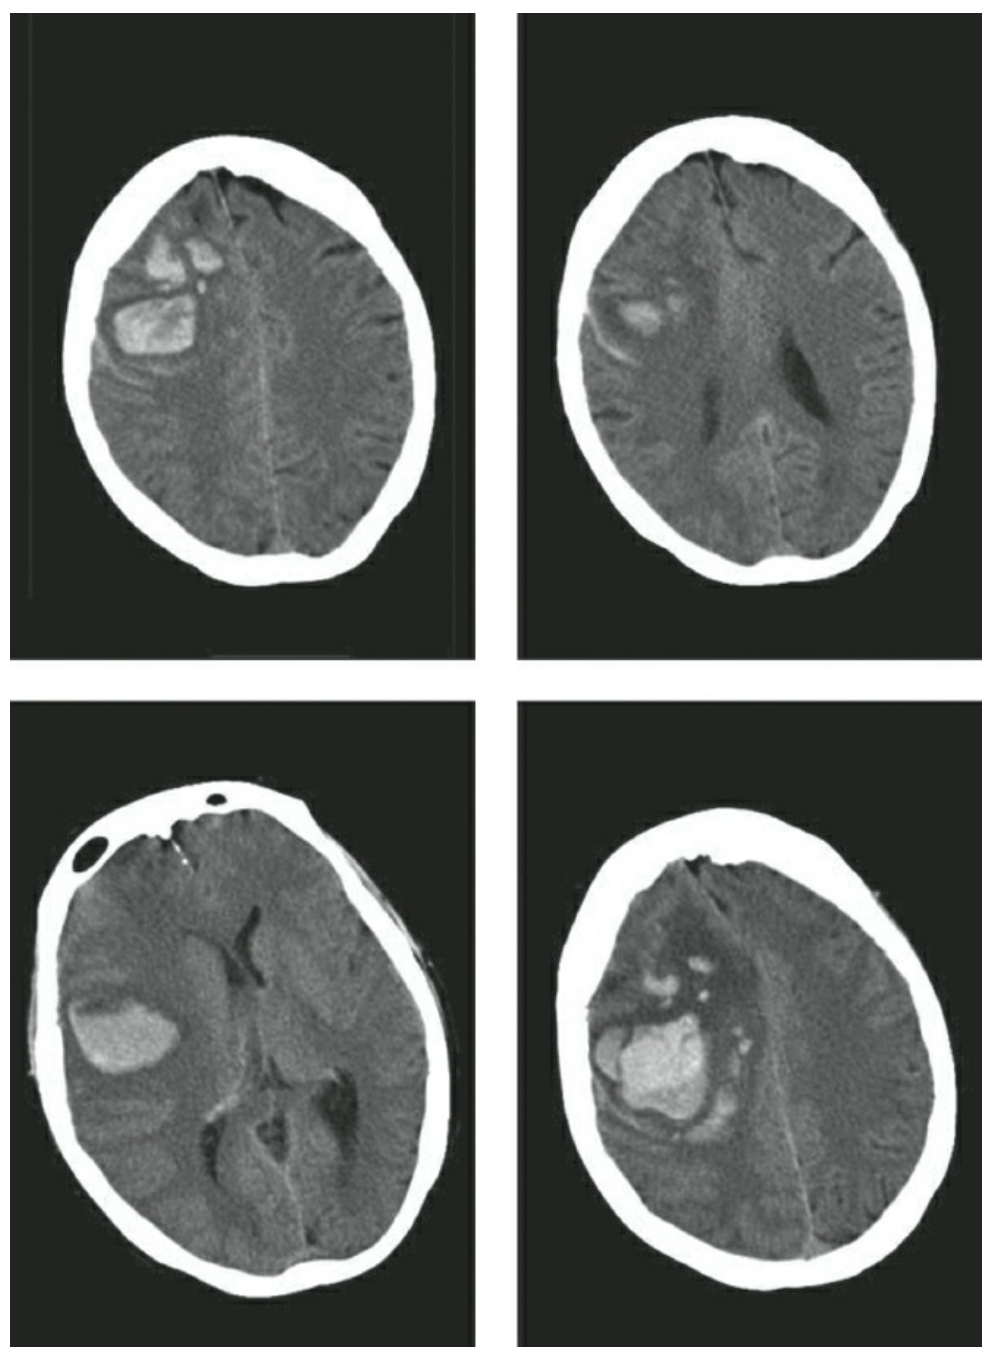

| Tăng huyết áp | Tiền sử và dấu hiệu tăng huyết áp | Vị trí đặc trưng: Hạch nền (55%), đồi thị (26%), bán cầu đại não (11%), cầu não (8%), tiểu não (7%) |

| Bệnh mạch máu não dạng bột(amyloid) | Tuổi cao hơn, tiền sử suy giảm nhận thức, TIA hoặc ICH trước đó | Bề ngoài, phân thùy; hình thành thùy, vỡ thành khoang dưới nhện hoặc màng cứng, xuất huyết não thất thứ phát; thường ở thái dương, chẩm; ít gặp ở tiểu não; “xuất huyết vi thể” trên MRI (T2*) |

| Sử dụng thuốc (Cocaine, Methamphetamine...) | Tuổi trẻ hơn, tiền sử sử dụng thuốc tác động lên hệ giao cảm | Kiểu dưới vỏ thường xuyên hơn và xuất huyết trong não thất |

| Rối loạn đông máu | Tiền sử sử dụng thuốc chống đông máu | Phân chia thùy, mức chất lỏng-chất lỏng trong khối máu tụ |

| Dị dạng mạch máu (AVM, dị dạng hang...), Rò động tĩnh mạch màng cứng | Bệnh nhân trẻ hơn (< 45 tuổi), huyết áp bình thường, tiền sử gia đình, co giật hoặc xuất huyết trước đó | CT-A hoặc DSA với những dấu hiệu điển hình |

| Bệnh Moyamoya | Người Mỹ gốc Phi, người châu Á, bệnh hồng cầu hình liềm. | Phun khói trên DSA |

| Chuyển dạng xuất huyết của đột quỵ thiếu máu cục bộ | Đột quỵ do thiếu máu cục bộ trước đó. | Các chấm xuất huyết, loang lổ, rải rác khắp vùng mô bị nhồi máu. Đường viền vùng nhồi máu dễ phác họa trên CT. |

| Huyết khối xoang tĩnh mạch não | Sản giật, mang thai | CT không thuốc cản quang tăng tỷ trọng vùng xoang, hoặc MR tĩnh mạch khiếm khuyết lấp đầy xoang |

| Khối u | Đã biết khối u nguyên phát | Phù đáng kể xung quanh xuất huyết cấp tính, ngấm thuốc cản quang xung quanh khối máu tụ. |